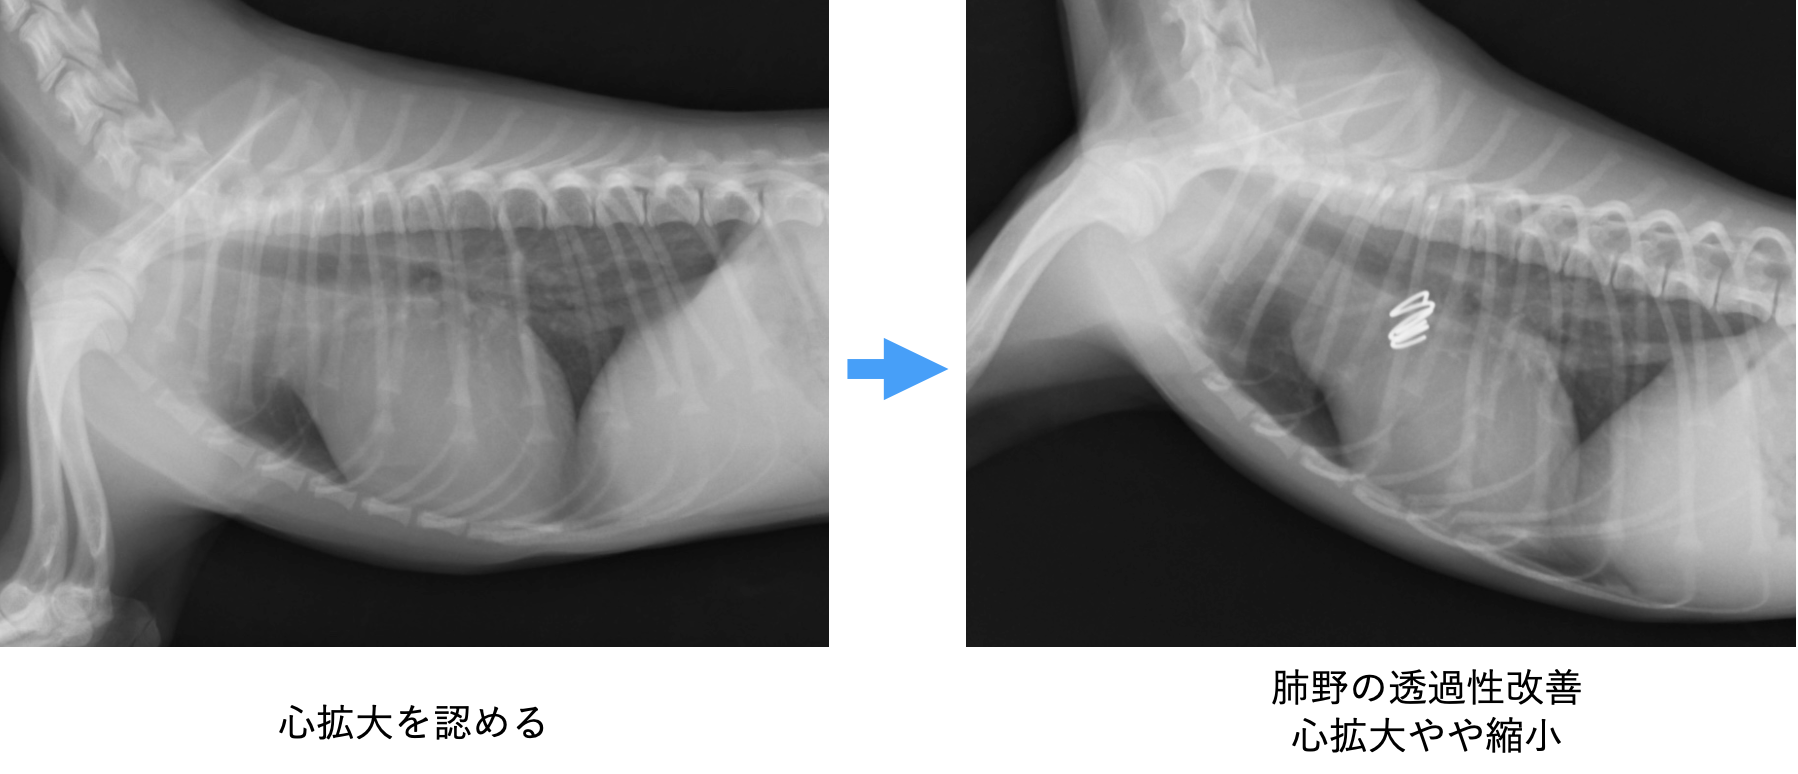

動脈管開存症は、生まれつきの心臓病で放っておいた場合の1年間での死亡率は70%と、致命率が非常に高い病気です。お母さんのお腹の中にいた時には、大事な役割をしていた動脈管が、出生後も血管が残ったままになってしまい、大動脈から全身に送り出される血液の大部分がが肺に流れ込んでしまう事態がおきます。すると、全身は血液が送られずに疲れやすく、肺は異常な量の血液が流れ込むので、鬱血という血液が大渋滞を起こすような状態になります。

酷くなると肺に水が溜まる肺水腫という左心不全症状が出現します。これは陸にいながら溺れているほど苦しい状態と言われております。

足の血管に小さく切開を実施し、カテーテルを心臓まで挿入。造影という血管を光らせる薬で動脈管をはっきりと描出し、タイプがコイルの適応であればコイルで治療できます。今回は造影後にコイルの適応タイプだったためそのままコイルを入れ手術終了。1hr30min程度でコイルひとつを入れ閉塞を確認したの後終了できています。

さて術後は3日もすると、元気に走り回れるようになり(開胸ではこうはいきません)、退院後のトラブルもなく完治となっています。